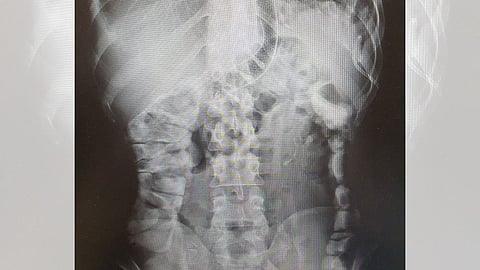

وأشارت سعود الطبية، إلى أن المريض كان يشكو سابقًا من سمنة حتى وصل وزنه إلى 150 كغ، ثم أصبح وزنه 41 كغ بعد عملية تكميم المعدة.

وأوضحت أنه تم وضع خطة علاجية شملت إجراء تصريف للصديد داخل البطن، ووضع دعامة تسمح بمرور الطعام، مكنته من تحسين وضعه الصحي خلال أيام.